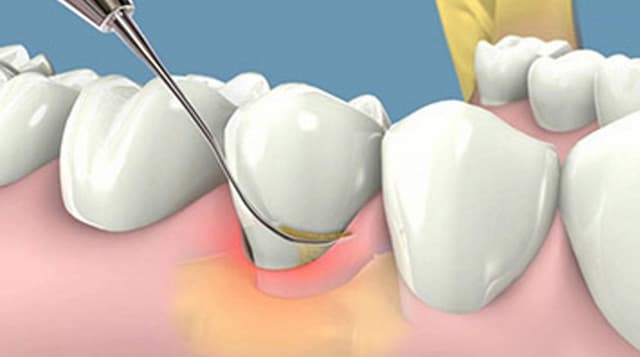

Cao răng ảnh hưởng không nhỏ tới sức khỏe răng miệng, là tác nhân gây ra một số bệnh lý nha khoa. Do đó, các bác sĩ luôn khuyến cáo mọi người cần lấy cao răng thường xuyên để bảo vệ sức khỏe hàm răng. Vậy thời gian lấy cao răng có lâu không, hãy […]

Chúng ta nghe nhiều về cụm từ “cao răng” nhưng không phải ai cũng hiểu rõ hệ lụy mà cao răng gây ra đối với sức khỏe răng miệng. Do vậy, các bác sĩ nha khoa luôn khuyến cáo mọi người cần lấy cao răng thường xuyên. Vậy, lấy cao răng có tác dụng gì […]